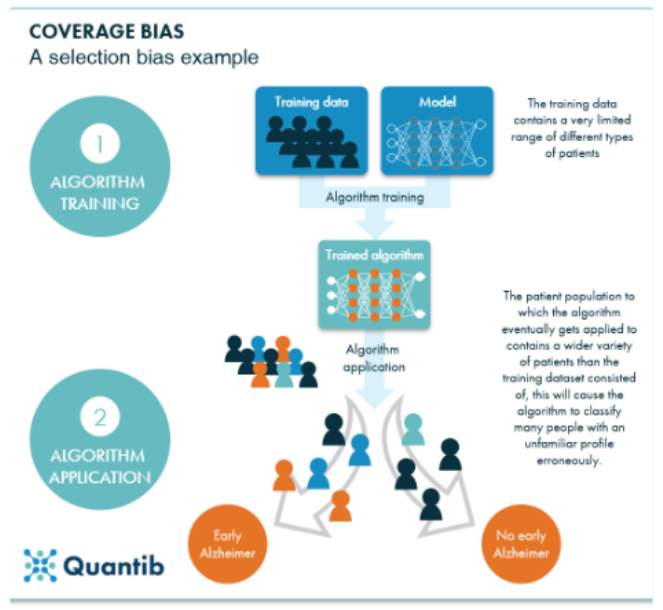

To understand how bias enters AI systems, let’s consider one type of bias, which is coverage bias illustrated by the figure above.

An AI program or algorithm is developed and trained using test data, which shapes its logic based on various data scenarios.

For the model above, the bias can be propagated by applying profiles erroneously due to a limited population of training data, compared to the more general population on which the model will be used.

Once tested, the AI program processes live data, providing results that are analyzed to further refine its logic. This feedback loop continues, allowing the machine to learn and evolve.